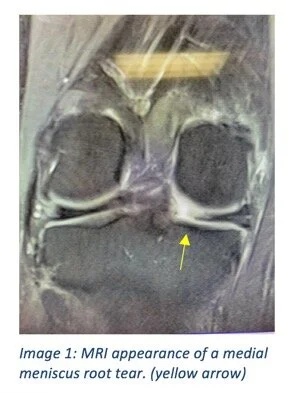

Although there are a number of different types of meniscus tears, meniscus root tears require particular attention and discussion. The attachments of the medial (inside) and lateral (outside) meniscus to the tibia are called the meniscus roots. These function to anchor the meniscus to the bone during weight bearing, allowing the meniscus to function properly. The root attachment is a critical part of the meniscus, and when torn, can have detrimental effects on the function and long-term health of the cartilage. When a meniscus root is torn, the remaining meniscus, although present, does not function and this scenario is equivalent to not having any meniscus at all. Because of this, the main concern with a meniscus root tear is the increased stress and load that will be placed on the cartilage of that compartment. Over time, this can lead to premature arthritis, and if severe, may require a joint replacement.